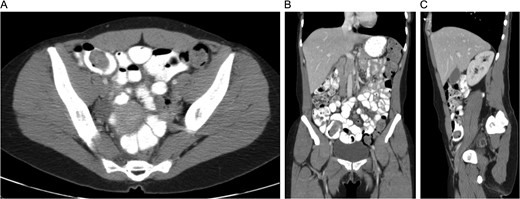

CT with oral and IV contrast demonstrated cecal thickening without visualization of the appendix (Fig. 1). A colonoscopy was performed, which showed mild diffuse erythema and edema in the last 40 cm of the ascending colon as well as a mass within the lumen of the cecum (Fig. 2). Biopsies of the colon demonstrated chronic active colitis and ulceration of the cecal mass, suggestive of mild UC (Fig. 3, bottom right and left). No granulomata were present, and there was no evidence of dysplasia. The decision was made for operative management due to continuation of her symptoms and need for definitive diagnosis.

CT with oral and IV contrast of the abdomen and pelvis in axial (A), coronal (B) and sagittal (C) views.